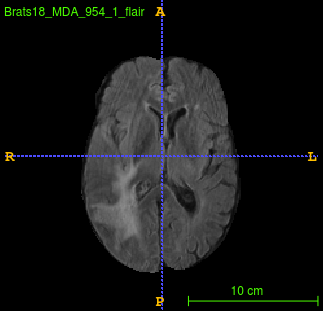

Segmentation of brain tumor from magnetic resonance imaging (MRI) is a vital process to improve diagnosis, treatment planning and to study the difference between subjects with tumor and healthy subjects. In this paper, we exploit a convolutional neural network (CNN) with hypercolumn technique to segment tumor from healthy brain tissue. Hypercolumn is the concatenation of a set of vectors which form by extracting convolutional features from multiple layers. Proposed model integrates batch normalization (BN) approach with hypercolumn. BN layers help to alleviate the internal covariate shift during stochastic gradient descent (SGD) training by zero-mean and unit variance of each mini-batch. Survival Prediction is done by first extracting features(Geometric, Fractal, and Histogram) from the segmented brain tumor data. Then, the number of days of overall survival is predicted by implementing regression on the extracted features using an artificial neural network (ANN). Our model achieves a mean dice score of 89.78%, 82.53% and 76.54% for the whole tumor, tumor core and enhancing tumor respectively in segmentation task and 67.90% in overall survival prediction task with the validation set of BraTS 2018 challenge. It obtains a mean dice accuracy of 87.315%, 77.04% and 70.22% for the whole tumor, tumor core and enhancing tumor respectively in the segmentation task and a 46.80% in overall survival prediction task in the BraTS 2018 test data set.